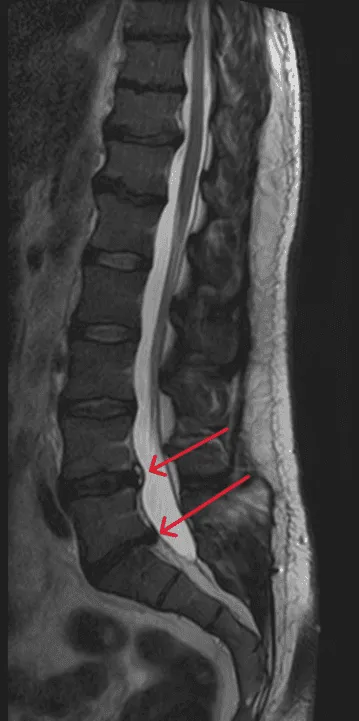

MRI of the lumbar spine with red arrows indicating areas of interest.

Recurrent Disc Herniation

Herniation reoccurs at the same or adjacent level despite disc replacement.